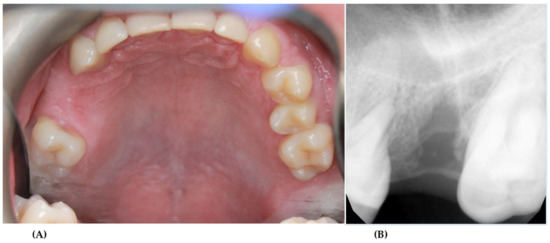

2. Case Presentation